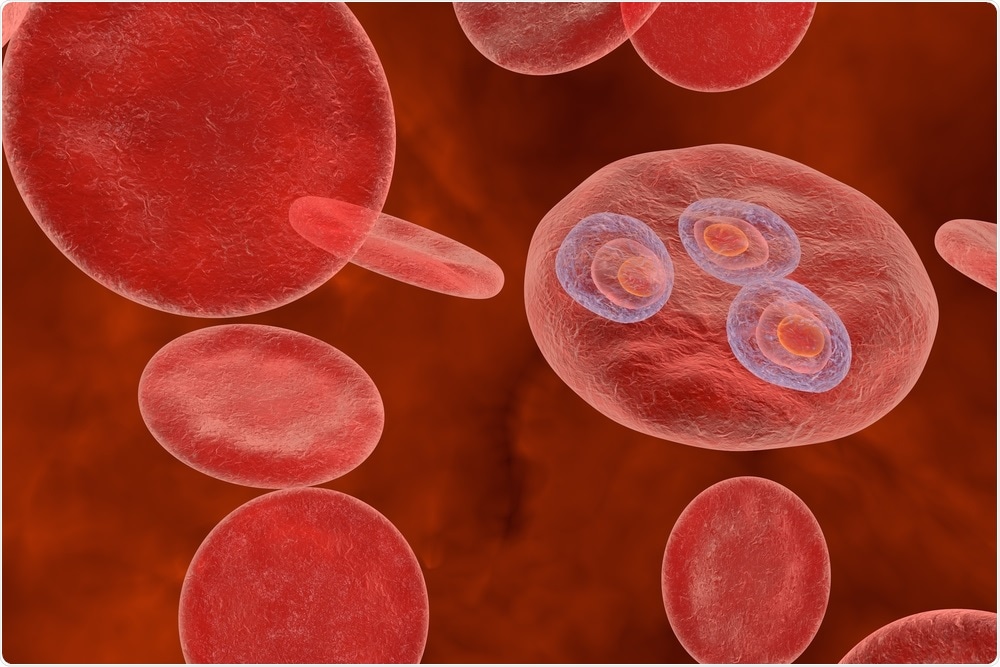

Image Credit: Kateryna Kon/Shutterstock.com

In addition to the protective action of the O blood group, the Dantu Hybrid Rearrangement stands out as another interesting alteration from what would be considered the “norm” for a red blood cell.

As a trait mostly confined to Eastern African countries, it confers up to a 74% reduction in the risk of severe malaria in individuals who are homozygous for this variant. Recent studies have found that the Dantu polymorphism causes extensive changes to arise in several different proteins found on the surface of RBCs.

Specifically, the expression of the glycophorin A (GYPA) intracellular domain was found to be altered in Dantu-individuals, which is significant, as GYPA plays a role in the invasion of P. falciparum merozoites into RBCs. Another observation in this study was that membrane tension is increased in Dantu RBCs, which might cause a greater proportion of the RBCs in these individuals to resist parasitic invasion.